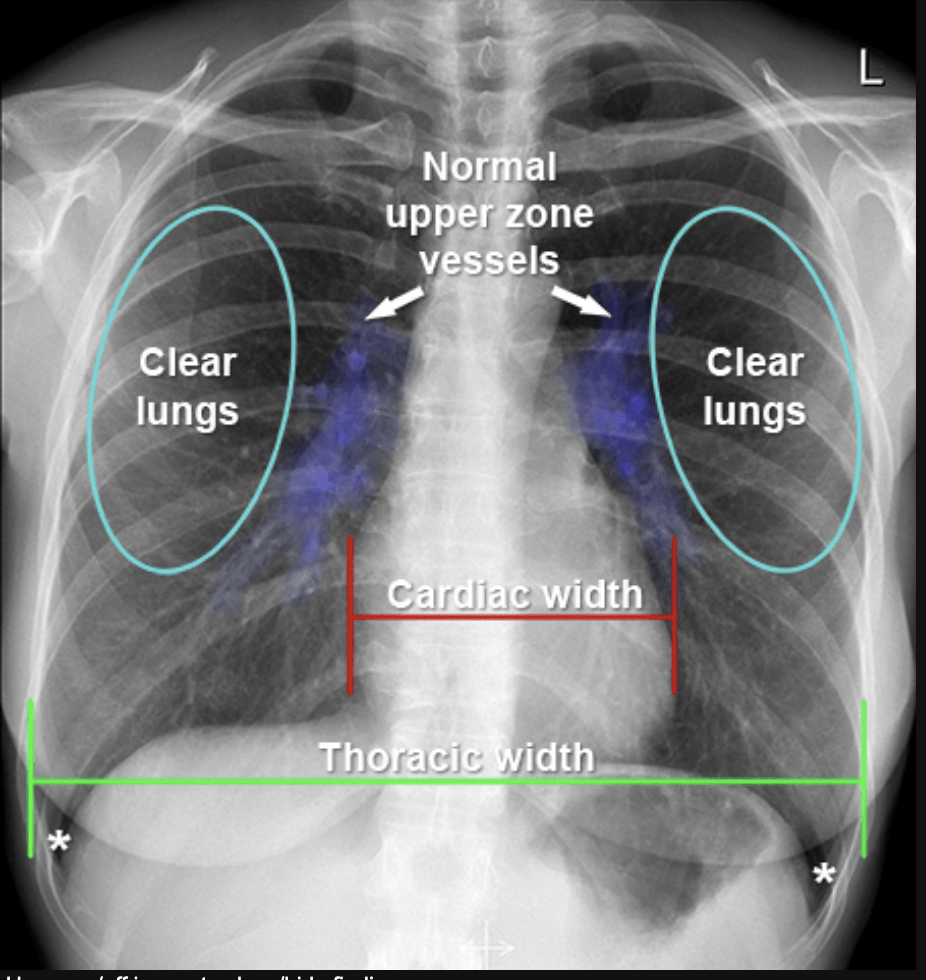

What do we look for in a CXR?

• How about this one?

Cardiomegaly - A big heart

• Water where it is not supposed to be.

Pleural Effusion

Chest Radiographs

Radiologists have a very strong mental model of what a CXR should look like